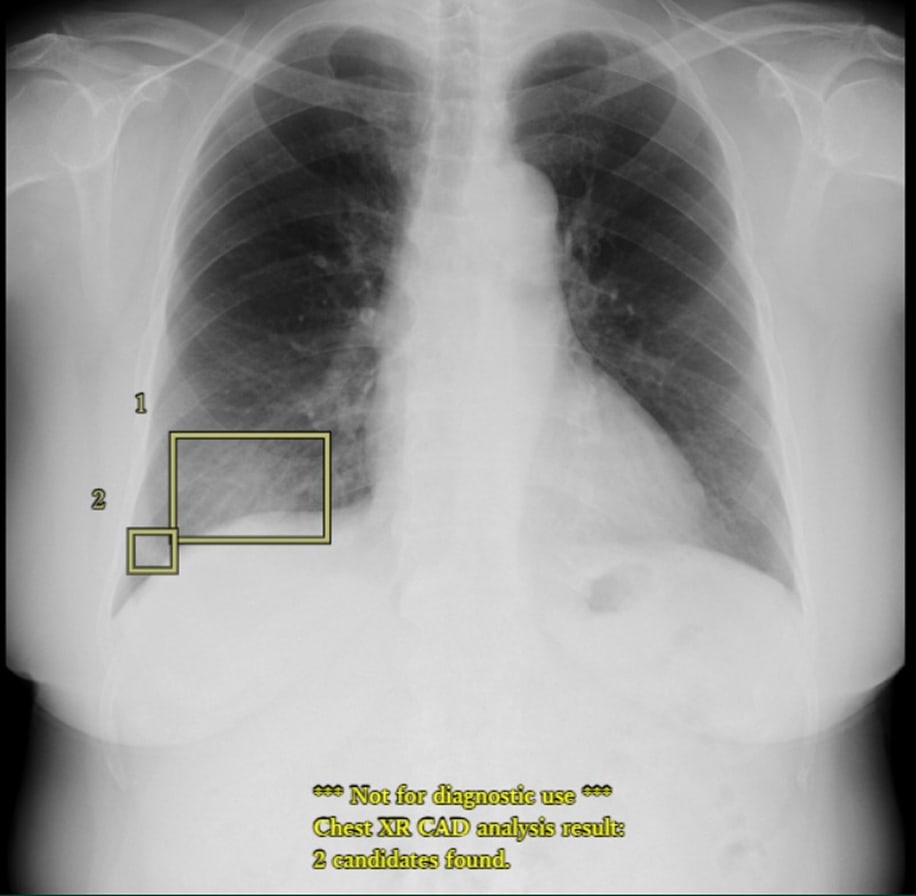

EIRL Cloud 利用イメージ

四角いボックスはEIRL Chest XR *1が検出した肺結節候補域❷と浸潤影候補領域❶を表示しています。

※EIRL Viewer *2による表示例です

*1 製造販売承認番号:30400BZX00285000 販売名:医用画像解析ソフトウェア EIRL Chest XR

*2 販売名:医用画像ビューワソフトウェア EIRL Viewer 製造販売認証番号:303AGBZX00046000